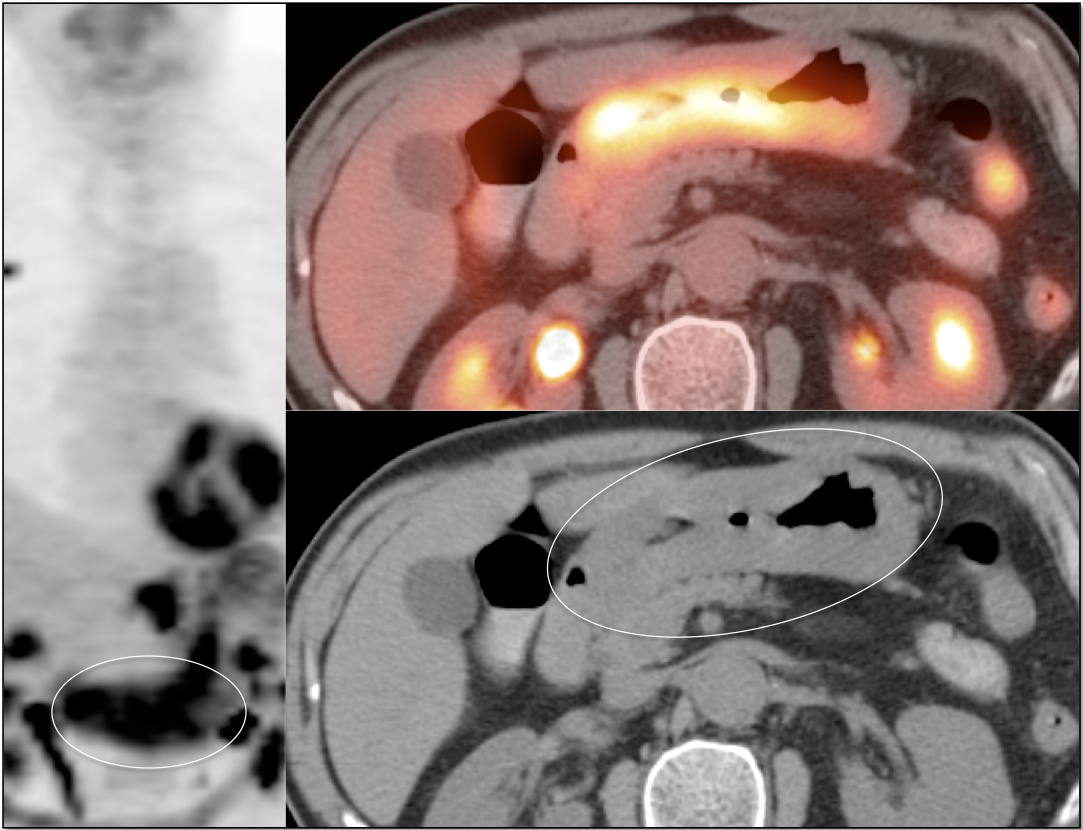

- Peritoneal Carcinomatosis